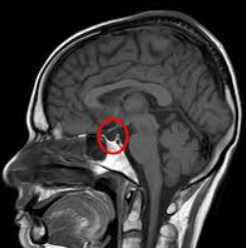

Visual acuity and visual field tests are a good screen to test for chiasmal involvement. Neuroimaging may also be needed (i.e. MRI (magnetic resonance imaging)). In some cases, endocrinologic evaluation should be considered when the cause is pituitary adenoma, which is the most common extrinsic cause of chiasmal syndrome. A pattern electroretinogram may be measured to predict the visual prognosis of patients with chiasmal compression.